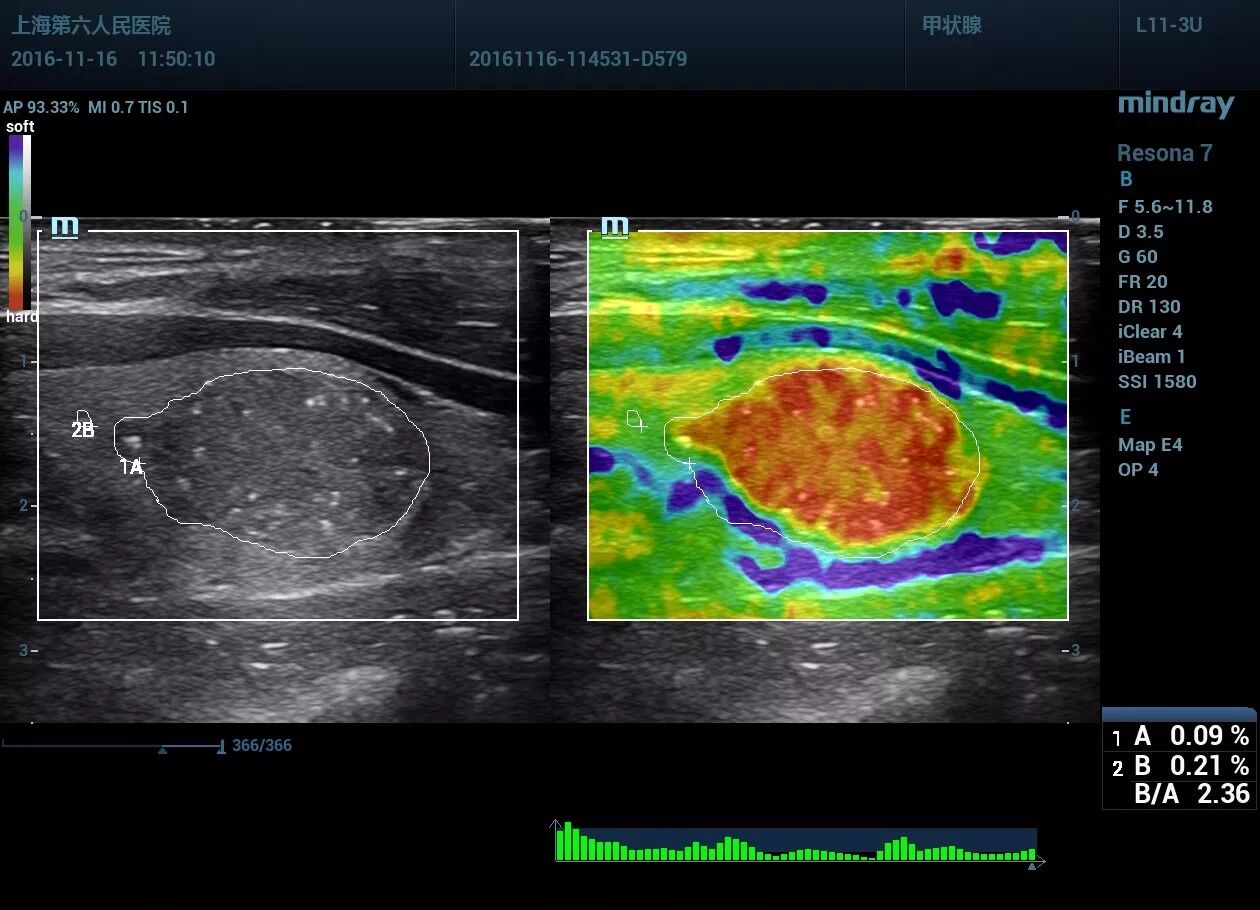

甲状腺左叶见一低回声区,大小约14*13*18mm,形态尚规则,部分边界欠清晰,内见点状强回声。CDFI显示血流信号丰富。左侧颈部VI区一淋巴结见高回声区。

应变式弹性评分:5分。剪切波弹性,横断面Emax94kpa,纵断面Emax123 kpa,远远大于良性病变的杨氏模量范围。纵切面显示肿块周边见深红色的不连续“硬环”。

1.甲状腺左叶实性结节伴微小钙化,弹性评分硬度高,考虑甲状腺Ca可能。